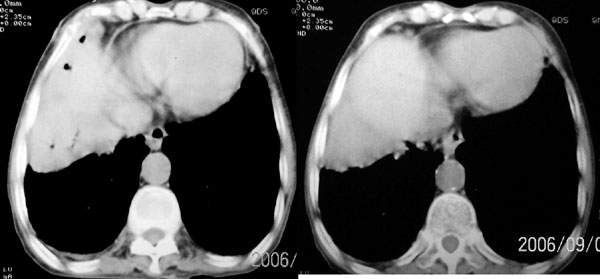

f 76 间断咳嗽 咳痰1年余 发热不明显 身体削瘦

征象:

1、右肺中叶近肺门区可见一空洞样病灶,内壁不规则,有与邻近支气管相通的征象,其外侧大片肺组织软组织状实变,余肺可见散在点、片絮状密度增高影,肺纹理可见明显增粗及串珠样改变;

2、纵隔气管前、隆突下、内乳组、心右前间隙以及右侧腋窝内均可见肿大的淋巴结节;

3、右侧胸膜增厚粘连,胸腔少量积液征像;

4、其它征像略。

诊断意见:

1、右侧中央型(空洞性)肺癌并双肺受累(包括转移、阻塞性炎症、癌性淋巴管炎);纵隔、右侧腋窝内淋巴结肿大、转移;右侧胸膜增厚粘连,胸腔少量积液;

2、双上肺陈旧性结核。

3、慢性支气管炎、肺气肿。